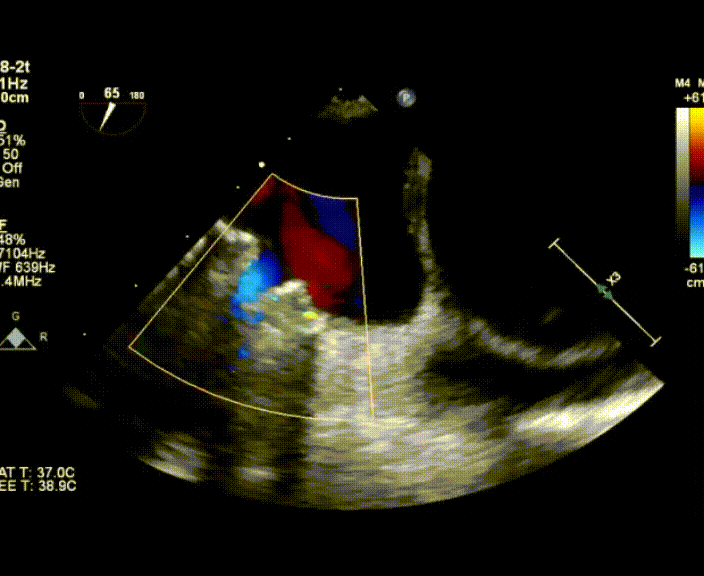

術中首先在局麻下穿刺股動脈、股靜脈,完成心導管檢查評估后轉為全麻,在食道超聲引導下穿刺房間隔,穿刺成功后將加硬導絲送入左上肺靜脈建立軌道,根據患者病情行球囊預擴張后植入6mm孔徑房間隔造孔支架,經透視及食道超聲評估支架左右盤展開良好,夾持于房間隔兩側,固定穩定、位置良好,食道彩超顯示房水平右向左為主分流,分流孔直徑符合預期大小,心導管檢查評估達到預期效果,釋放造孔支架。術后12h患者下床活動,恢復順利,擬于近日完善術后評估后出院。

心房分流術是通過器械制造穩定可控的心房間分流,適應證包括藥物治療效果不佳的左心衰或肺動脈高壓右心衰。本例患者為肺動脈高壓右心衰,術中成功放置MicroFlux®造孔支架在房間隔理想位置上,創造穩定可控的心房間分流(此例患者以右向左分流為主),在不顯著增加左心負擔的情況下,有效降低患者右心房壓力、緩解體循環淤血,增加左心輸出量,改善患者癥狀、活動耐力和生存質量。同時,國內外也已經開展多項房間隔造孔支架在射血分數保留、射血分數中間值和射血分數降低的左心衰患者中的臨床研究,結果顯示對于經過充分的規范化藥物治療后仍控制不佳的患者,心房分流術可改善患者的癥狀及生存質量?! ?/p>